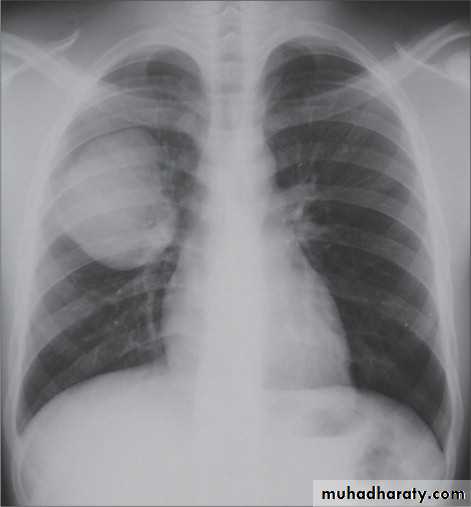

Pleural effusion

Pleural effusion tends to be used as a catch-all term denoting a collection of fluid within the pleural space. This can be further divided into exudates and transudates depending on the biochemical analysis of aspirated pleural fluid. Essentially it represents any pathological process which overwhelms the pleura's ability to reabsorb fluid.Radiographic appearances

Plain radiographChest radiographs are the most commonly used examination to assess for presence of a pleural effusion, however it should be noted that on a routine erect chest x-ray as much as 250-600 ml of fluid is required before it becomes evident 6. A lateral decubitus film is most sensitive, able to identify even a small amount of fluid. At the other extreme, supine films can mask large quantities of fluid.

A subpulmonic effusion (infrapulmonary effusion) may be seen when there is previously established pulmonary disease, but can also be encountered in normal lungs , They are more common on the right, and usually unilateral

with large volume effusions, mediastinal shift occurs away from the effusion (note: if coexistent collapse dominates then mediastinal shift may occur towards the effusion)